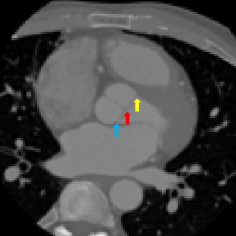

Finally, the proposed network was evaluated for the detection of five additional landmarks: the left coronary ostium, the bifurcation of the LM into the LAD and the LCx, and the origin of the left, non-coronary, and right aortic valve commissures (see Fig. 2). Fig 3 shows vector fields visualizing the predicted displacement vectors in three viewing planes in an image from the test set (for more results, see Appendix). Table 3 lists the Euclidean distance errors between the predicted landmark locations and the reference landmark locations. In addition, box-and-whiskers plots are shown in Fig 4. The best results were obtained for the origin of the right aortic valve commissure. Detection of the origin of the left aortic valve had the most narrow distribution. Outliers were seen during detection of the right ostium, the bifurcation of the LM, and the origin of the non-coronary, and the left aortic valve commissure.

Figure 2: Axial slices from a CCTA scan, resized to an isotropic voxel size of 1.5 mm, in which reference landmark locations are indicated with a colored arrow. The landmarks shown are the left coronary ostium (left), the bifurcation of the LM in the LAD and the LCx (middle left), the right coronary ostium (middle right), and the origin of the right (yellow arrow), non-coronary (red arrow) and left (blue arrow) aortic valve commissure (right).